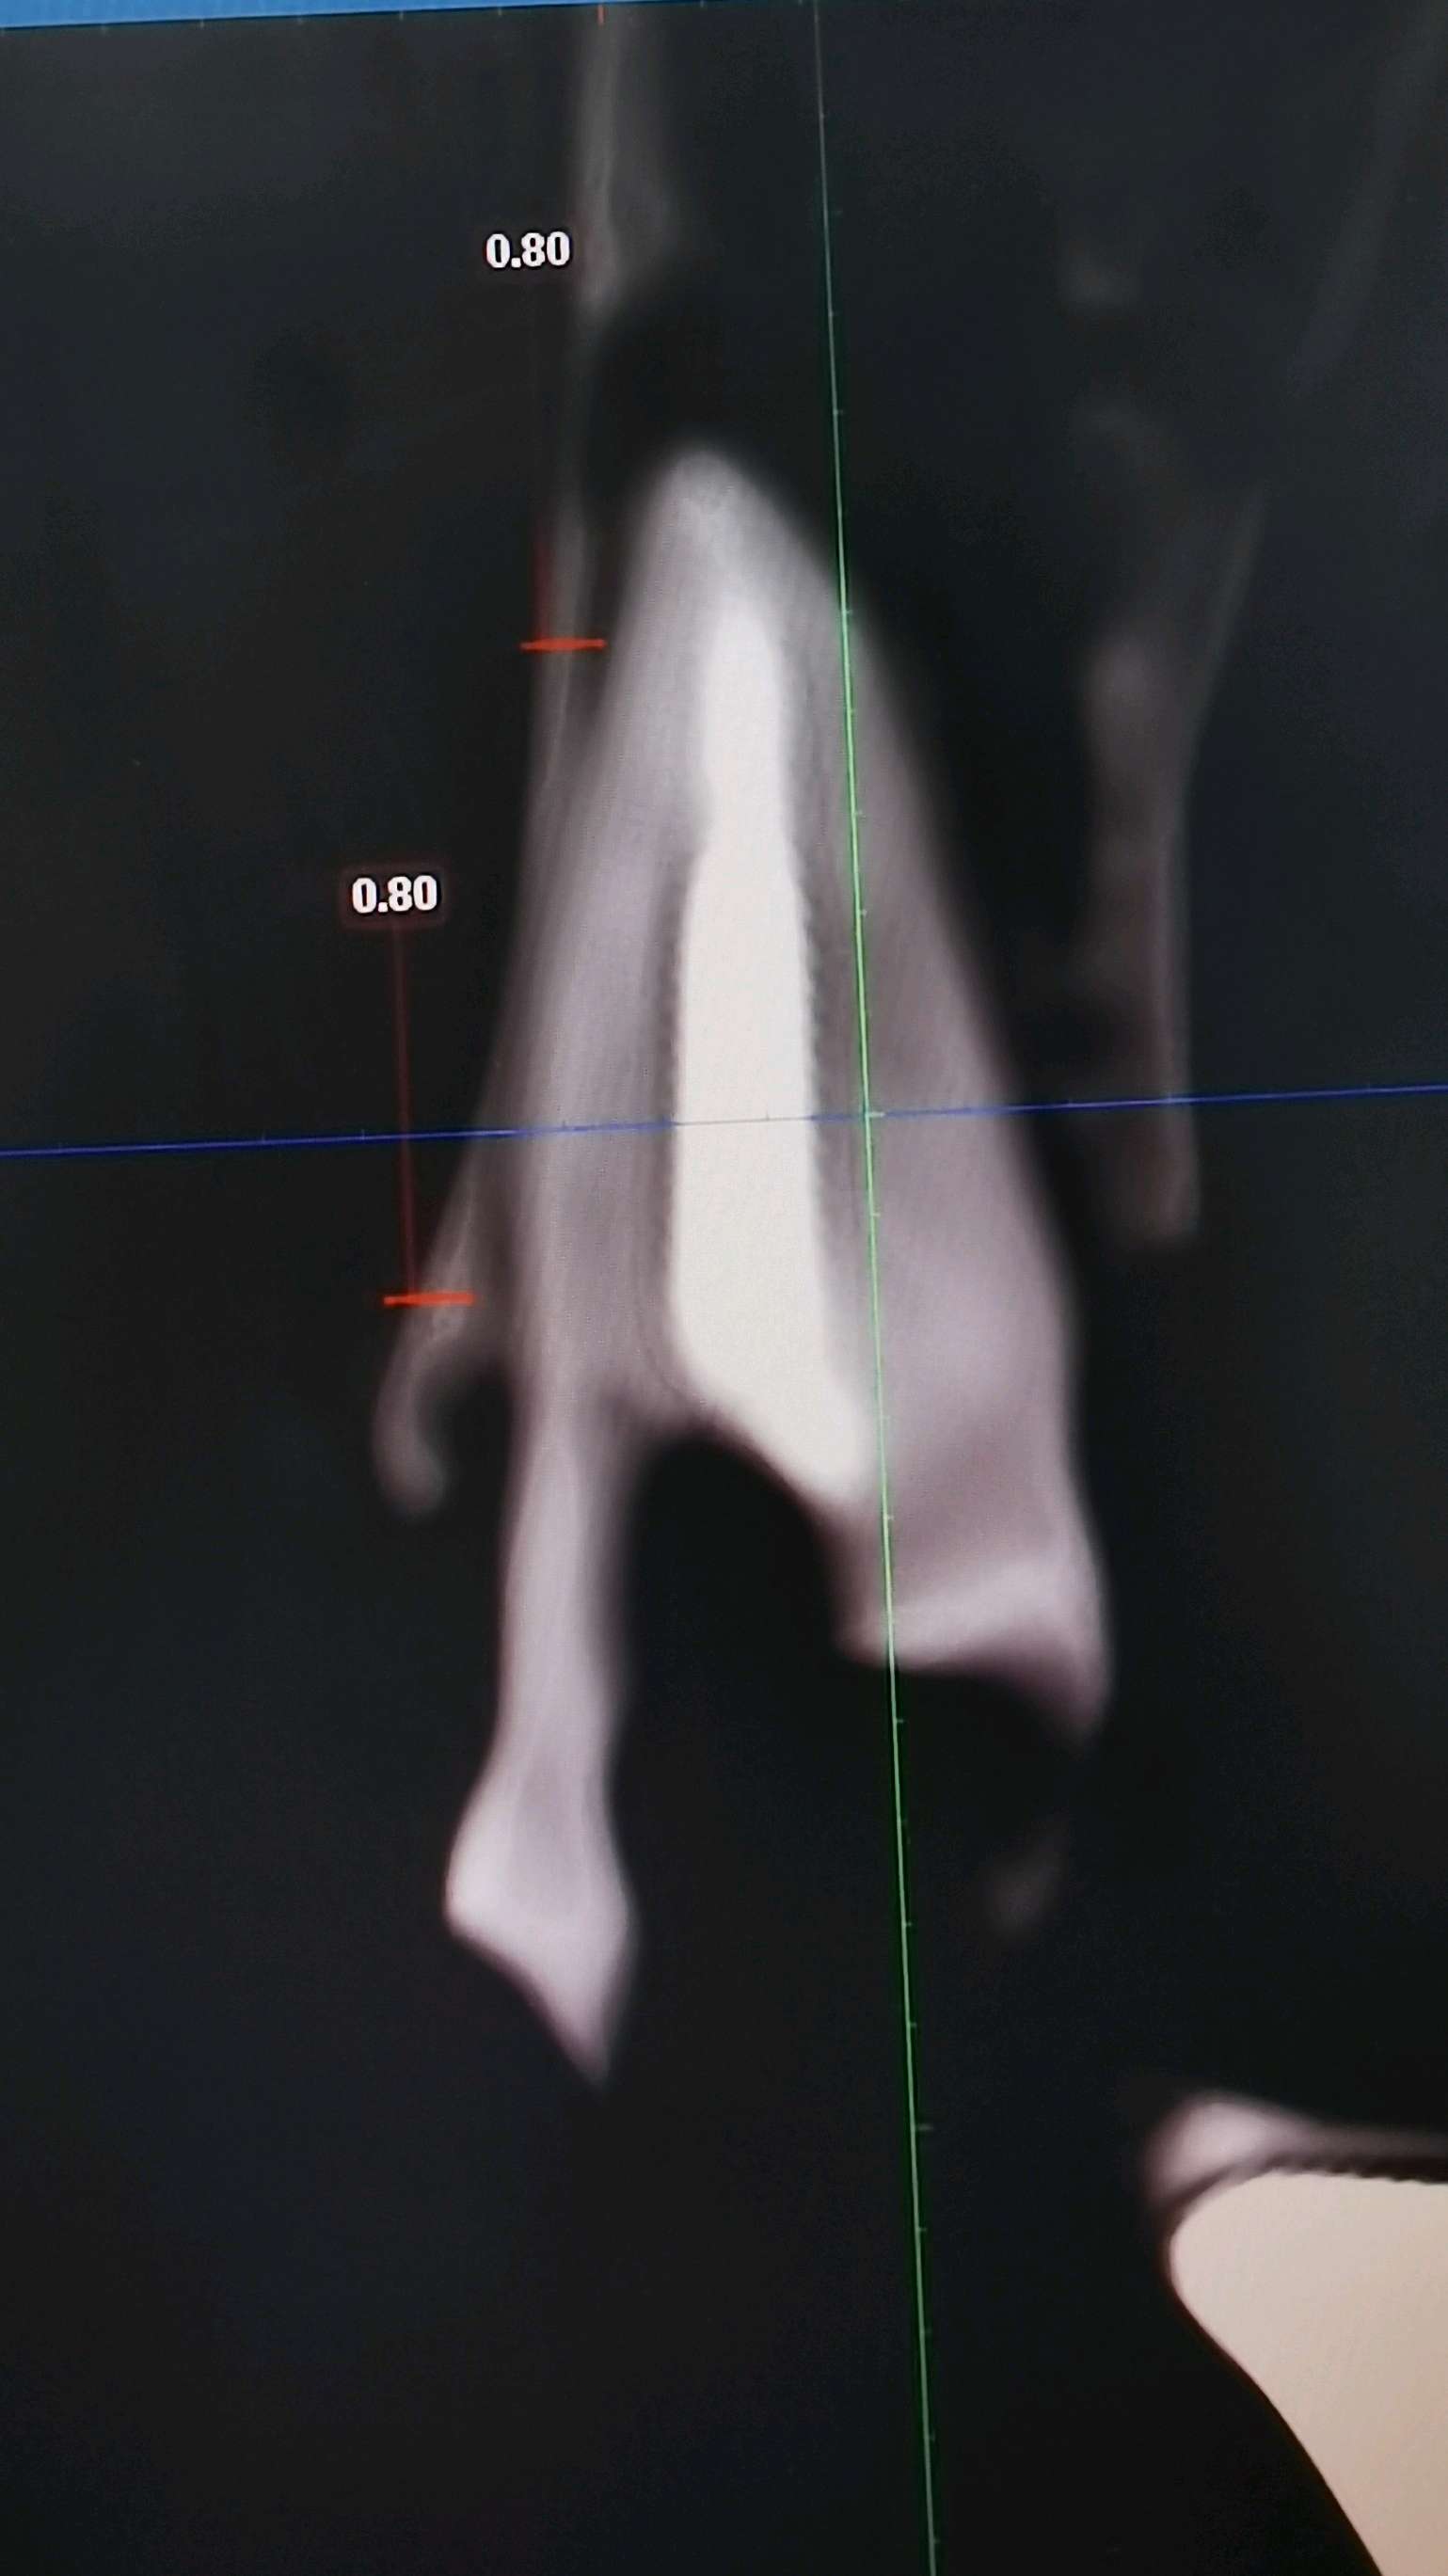

a.术前准备拍摄颌面部 CBCT ,评估骨质骨量,设计种植体植入的位置、轴向、直径和长度。

c、即刻植入根据拔牙窝的位置方向和颌骨的解剖形态,将钻头方向贴着腭侧骨板,采用逐级备洞的方法制备种植窝,植入适当长度和直径的种植体。即刻修复如种植体初期稳定性≥35N/ cm ,可行即刻修复。术中行数字化无痛印模,送工厂行高精度义齿制作,1周内复诊,行义齿戴入,所有即刻修复体均调整至正中、前伸和侧方咬合均无接触。根据种植愈合情况,即刻修复3-6个月后再行永久修复

案例左上2号根尖囊肿

根尖黄豆大小囊肿伴根纵折

3.5倍显微镜下拔牙,刮囊肿,植入ITI 种植体。